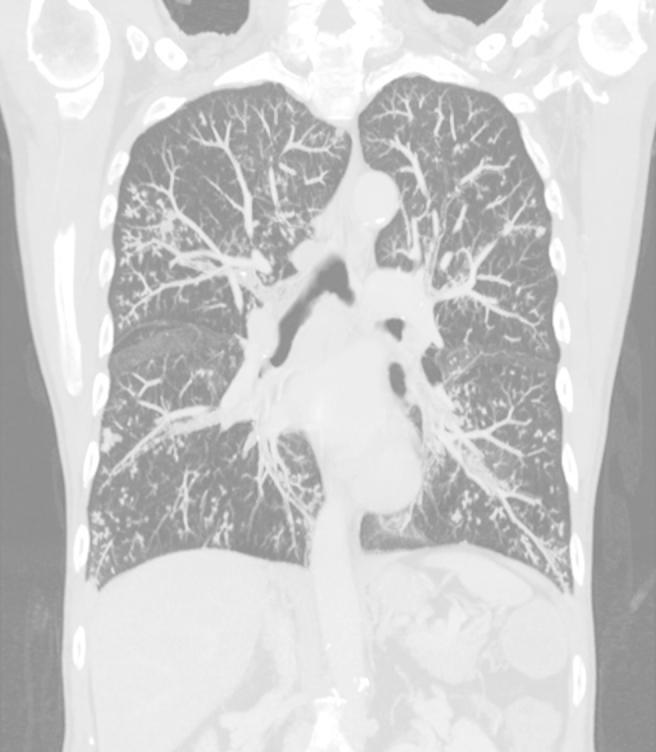

A 62-year-old man with asthma sought care for intermittent fever, cough with expectoration, breathlessness and orthopnoea with grunting. Computed tomography revealed clusters of centrilobular nodules on both sides with a tree-in-bud appearance and mild diffuse bronchial wall thickening. Sputum sample grew pure colonies of which was confirmed by MALDI-TOF and 16SrRNA gene sequencing. A. ureae may be an additional bacteriologic causative agent of the tree-in-bud pattern on computed tomographic scan.

一名62岁的哮喘男性因间歇性发热、咳痰咳嗽、呼吸急促和端坐呼吸伴呼噜声前来就诊。计算机断层扫描显示双侧有小叶中心结节簇,呈树芽征,伴有轻度弥漫性支气管壁增厚。痰标本培养出纯菌落,经基质辅助激光解吸电离飞行时间质谱(MALDI-TOF)和16SrRNA基因测序证实。脲原体可能是计算机断层扫描上树芽征模式的另一种细菌病原体。